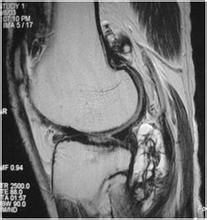

3:MRI組織解析度高能顯示病變的全部形態類型及組織成分PVNS的典型表現是T1WIT2WI均呈低信號,此特點的病理基礎是結節中含鐵血黃素的沉積,但病變早期關節內僅表現為出血結節中沒有或少有含鐵血黃素沉積,病變後期含鐵血黃素被吸收轉運而減少,因此這種信號特點並不貫穿病變全過程。